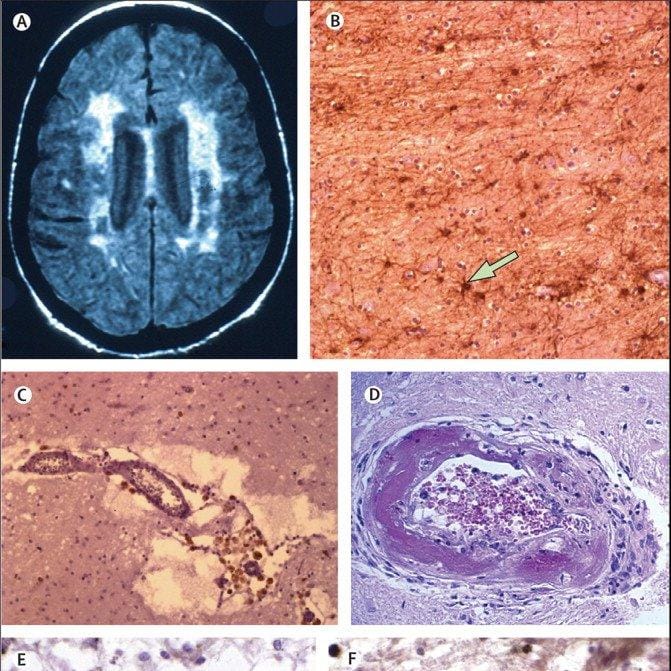

Binswanger's disease Rankings & Opinions